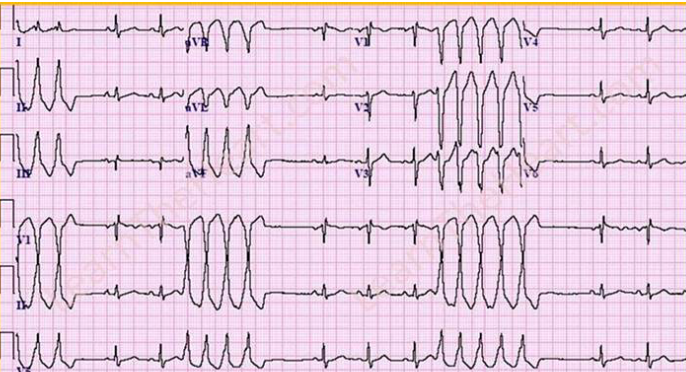

Case 3

A) What is ur diagnosis?

A) What is ur diagnosis?

Complete heart Block.

B) Treatment? Pacemaker

Case 4

Ventricular Tachycardia - Abnormal QRS complex

Ventricular Tachycardia - Abnormal QRS complex